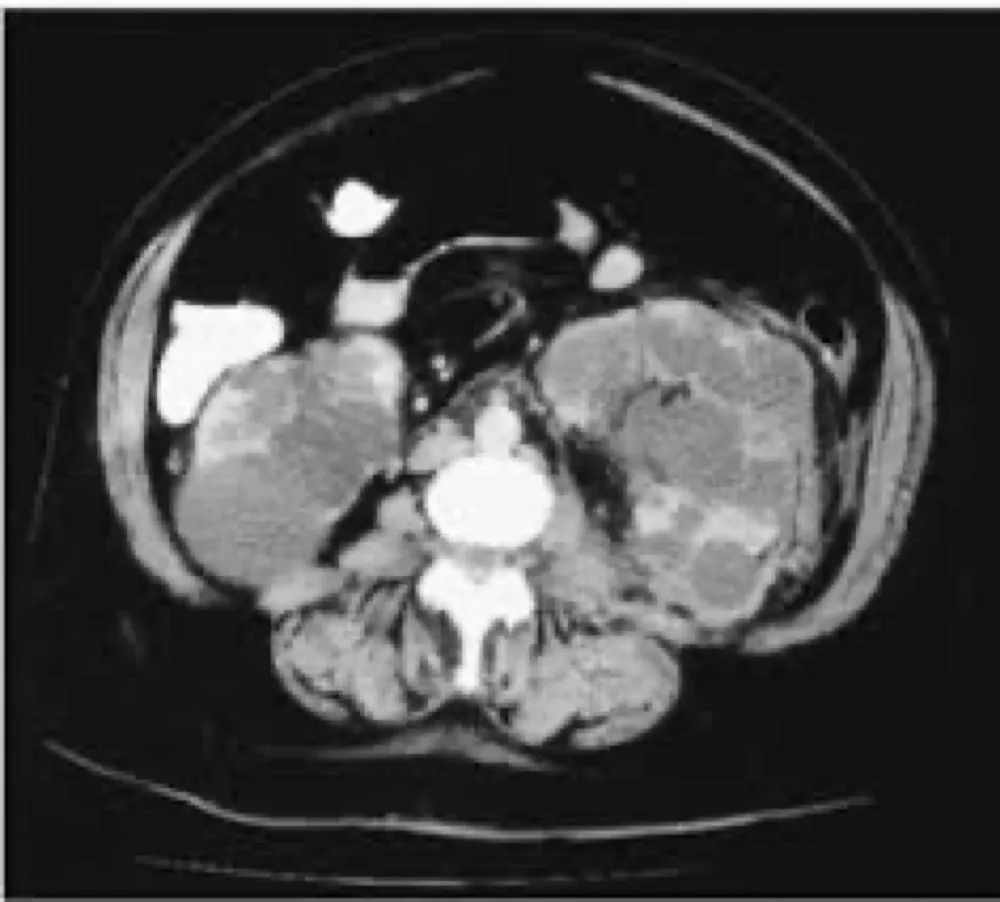

Injúria Renal Aguda (revisão Lancet 2025)